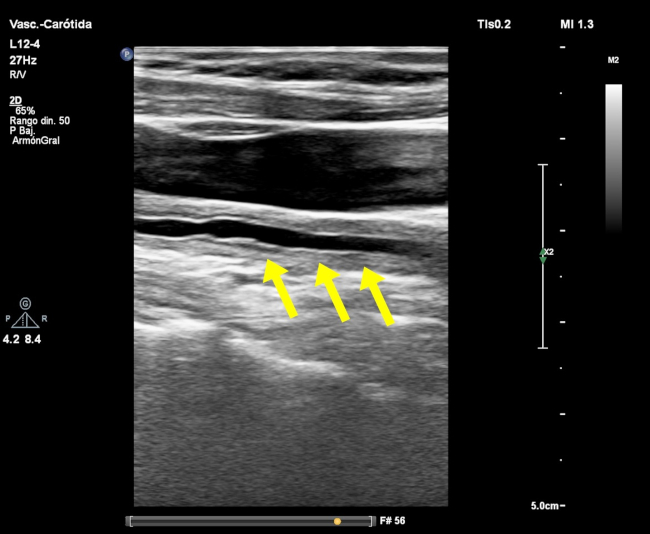

El signo del macarrón fue descrito por primera vez por Hiroaki Maeda en 1991. En su estudio de 23 pacientes con diagnóstico de arteritis de Takayasu (AT), demostró el engrosamiento difuso del complejo mio-intimal con ecografía modo-B en 19 pacientes.1 El engrosamiento parietal homogéneo de la carótida (►Fig. 1 y ►Fig. 2) se asemeja a un tipo de pasta, el macarrón, de característica forma tubular (►Fig. 3).

El análisis de la pared arterial mediante ecografía muestra la presencia de dos líneas ecogénicas paralelas, separadas por un espacio hipoecoico o anecoico. La línea ecogénica interna se corresponde la transición luz-íntima, siendo la línea más externa correspondiente a la interfase media-adventicia. El espacio comprendido entre ambas líneas ecogénicas se corresponde al engrosamiento combinado de la íntima y la media. El engrosamiento difuso y circunferencial de la arteria carótida permite observar el signo del macarrón, que es difícil de reconocer mediante angiografía.2